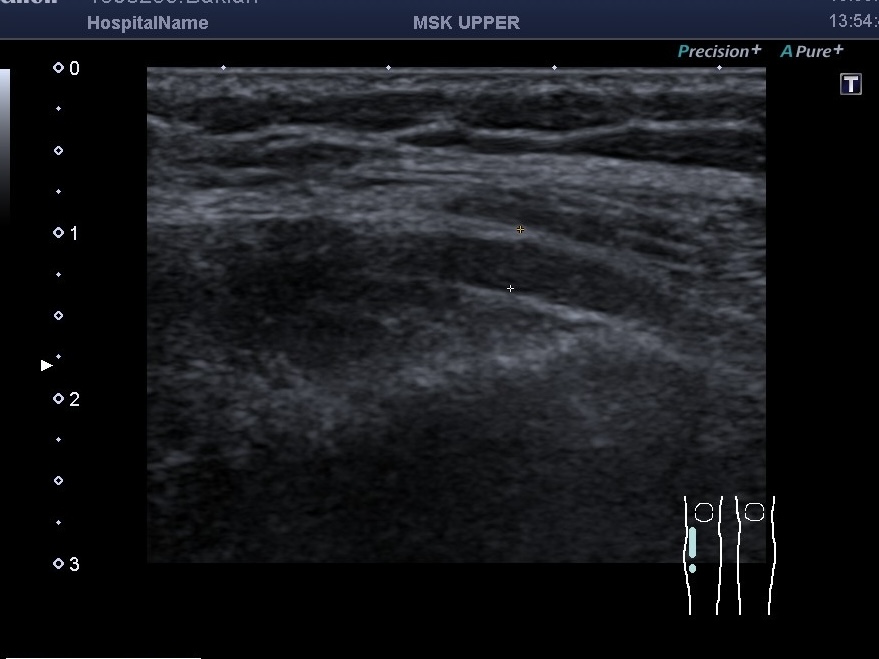

Интересные патологии нервов не исчезают и бывают даже среди детей. Например, на скане видна компрессия общего малоберцового нерва у девочки 16 лет аномально большой головкой малоберцовой кости при перескакивании нерва через эту головку. При этом часть волокон нерва увеличены, отекшие, а часть- нормальной структуры. При этом из клинических симптомов было нарушение только двигательной функции ноги (стопа висит), а чувствительность сохранена. Симптомы у девочки увеличивались в процессе ее роста — росла головка кости и еще больше сдавливала нерв. С помощью УЗД нервов мы можем выявить причину таких клинических симптомов и направить пациента к специалистам, которые исправят первопричину.